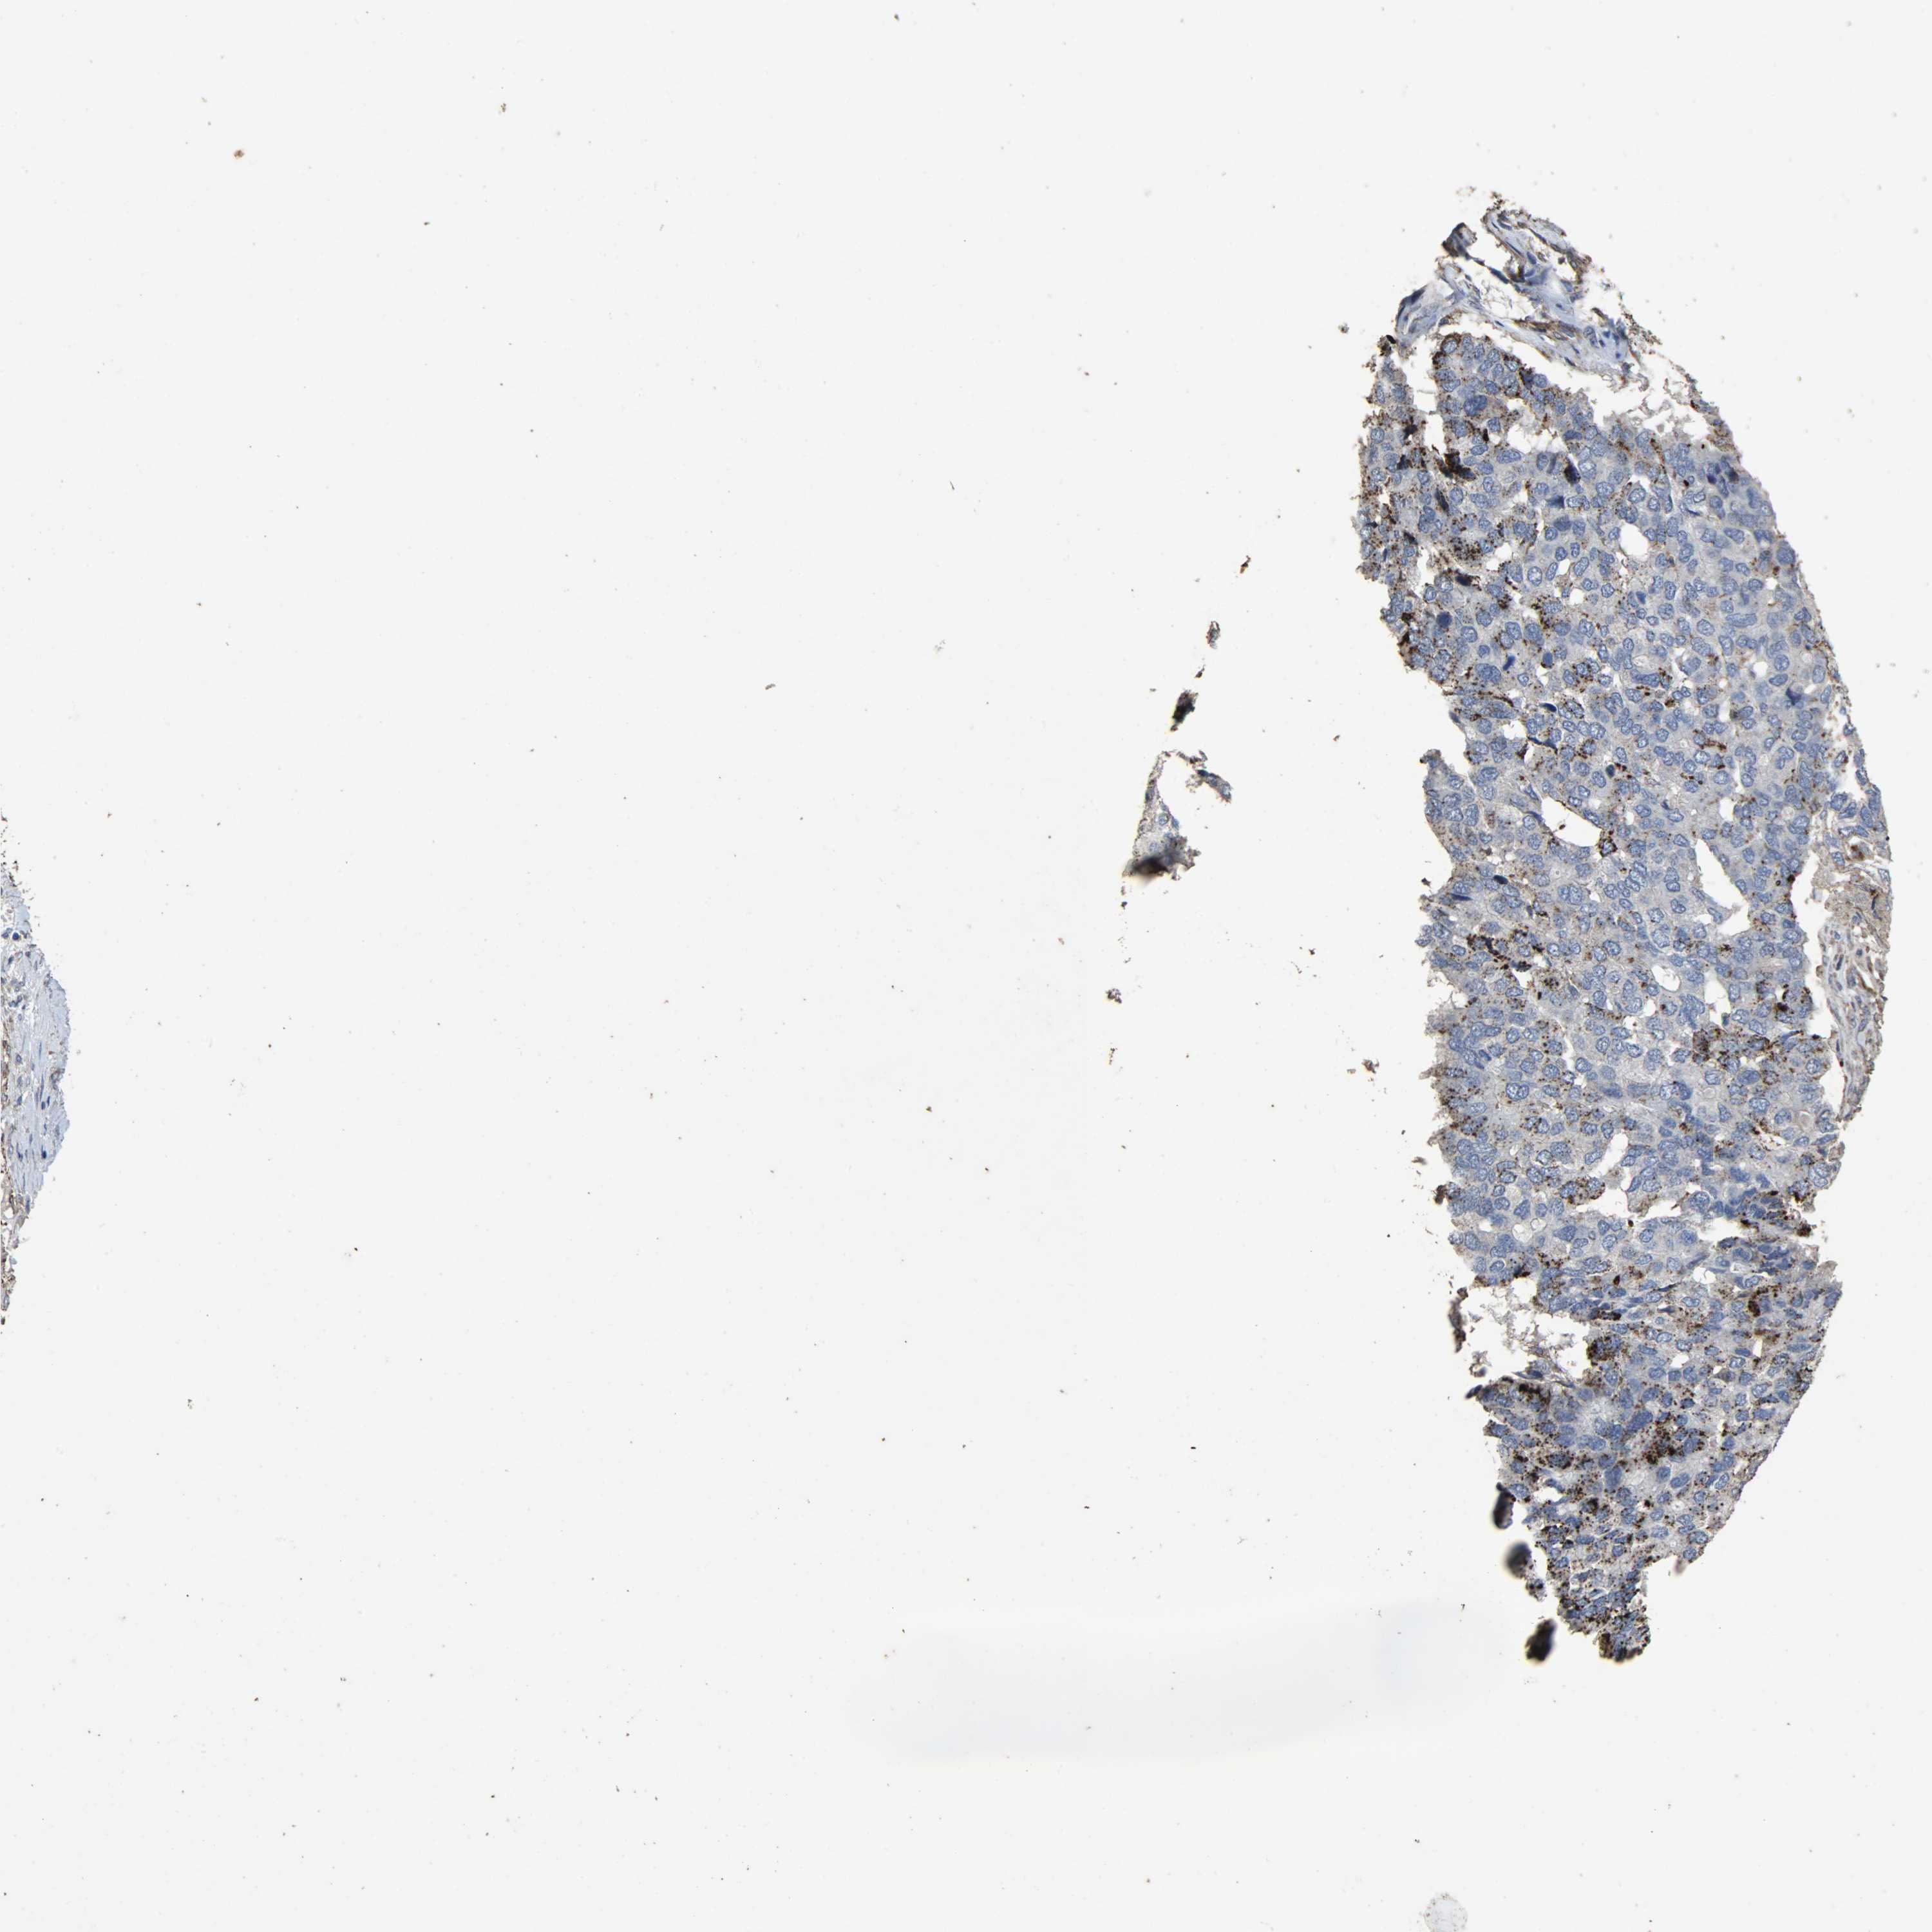

PANCREATIC CANCER - Protein expressioni

A mouse-over function shows sample information and annotation data. Click on an image to view it in a full screen mode. Samples can be filtered based on level of antibody staining by selecting one or several of the following categories: high, medium, low and not detected. The assay and annotation is described here.

Note that samples used for immunohistochemistry by the Human Protein Atlas do not correspond to samples in the TCGA dataset.

Antibody stainingi

Antibody staining in the annotated cell types in the current human tissue is reported as not detected, low, medium, or high, based on conventional immunohistochemistry profiling in selected tissues. This score is based on the combination of the staining intensity and fraction of stained cells.

Each image is clickable and will lead to virtual microscopy that enables deeper exploration of all samples and also displays staining intensity scores, fraction scores and subcellular localization as well as patient and tissue information for each sample.

Antibody HPA047089

Antibody HPA053624

Antibody CAB004685

Staining

High

Medium

Low

Not detected

Intensity

Strong

Moderate

Weak

Negative

Quantity

>75%

75%-25%

<25%

None

Location

Nuclear

Cytoplasmic/membranous

Cytoplasmic/membranous,nuclear

Adenocarcinoma, NOS

Adenocarcinoma, metastatic, NOS